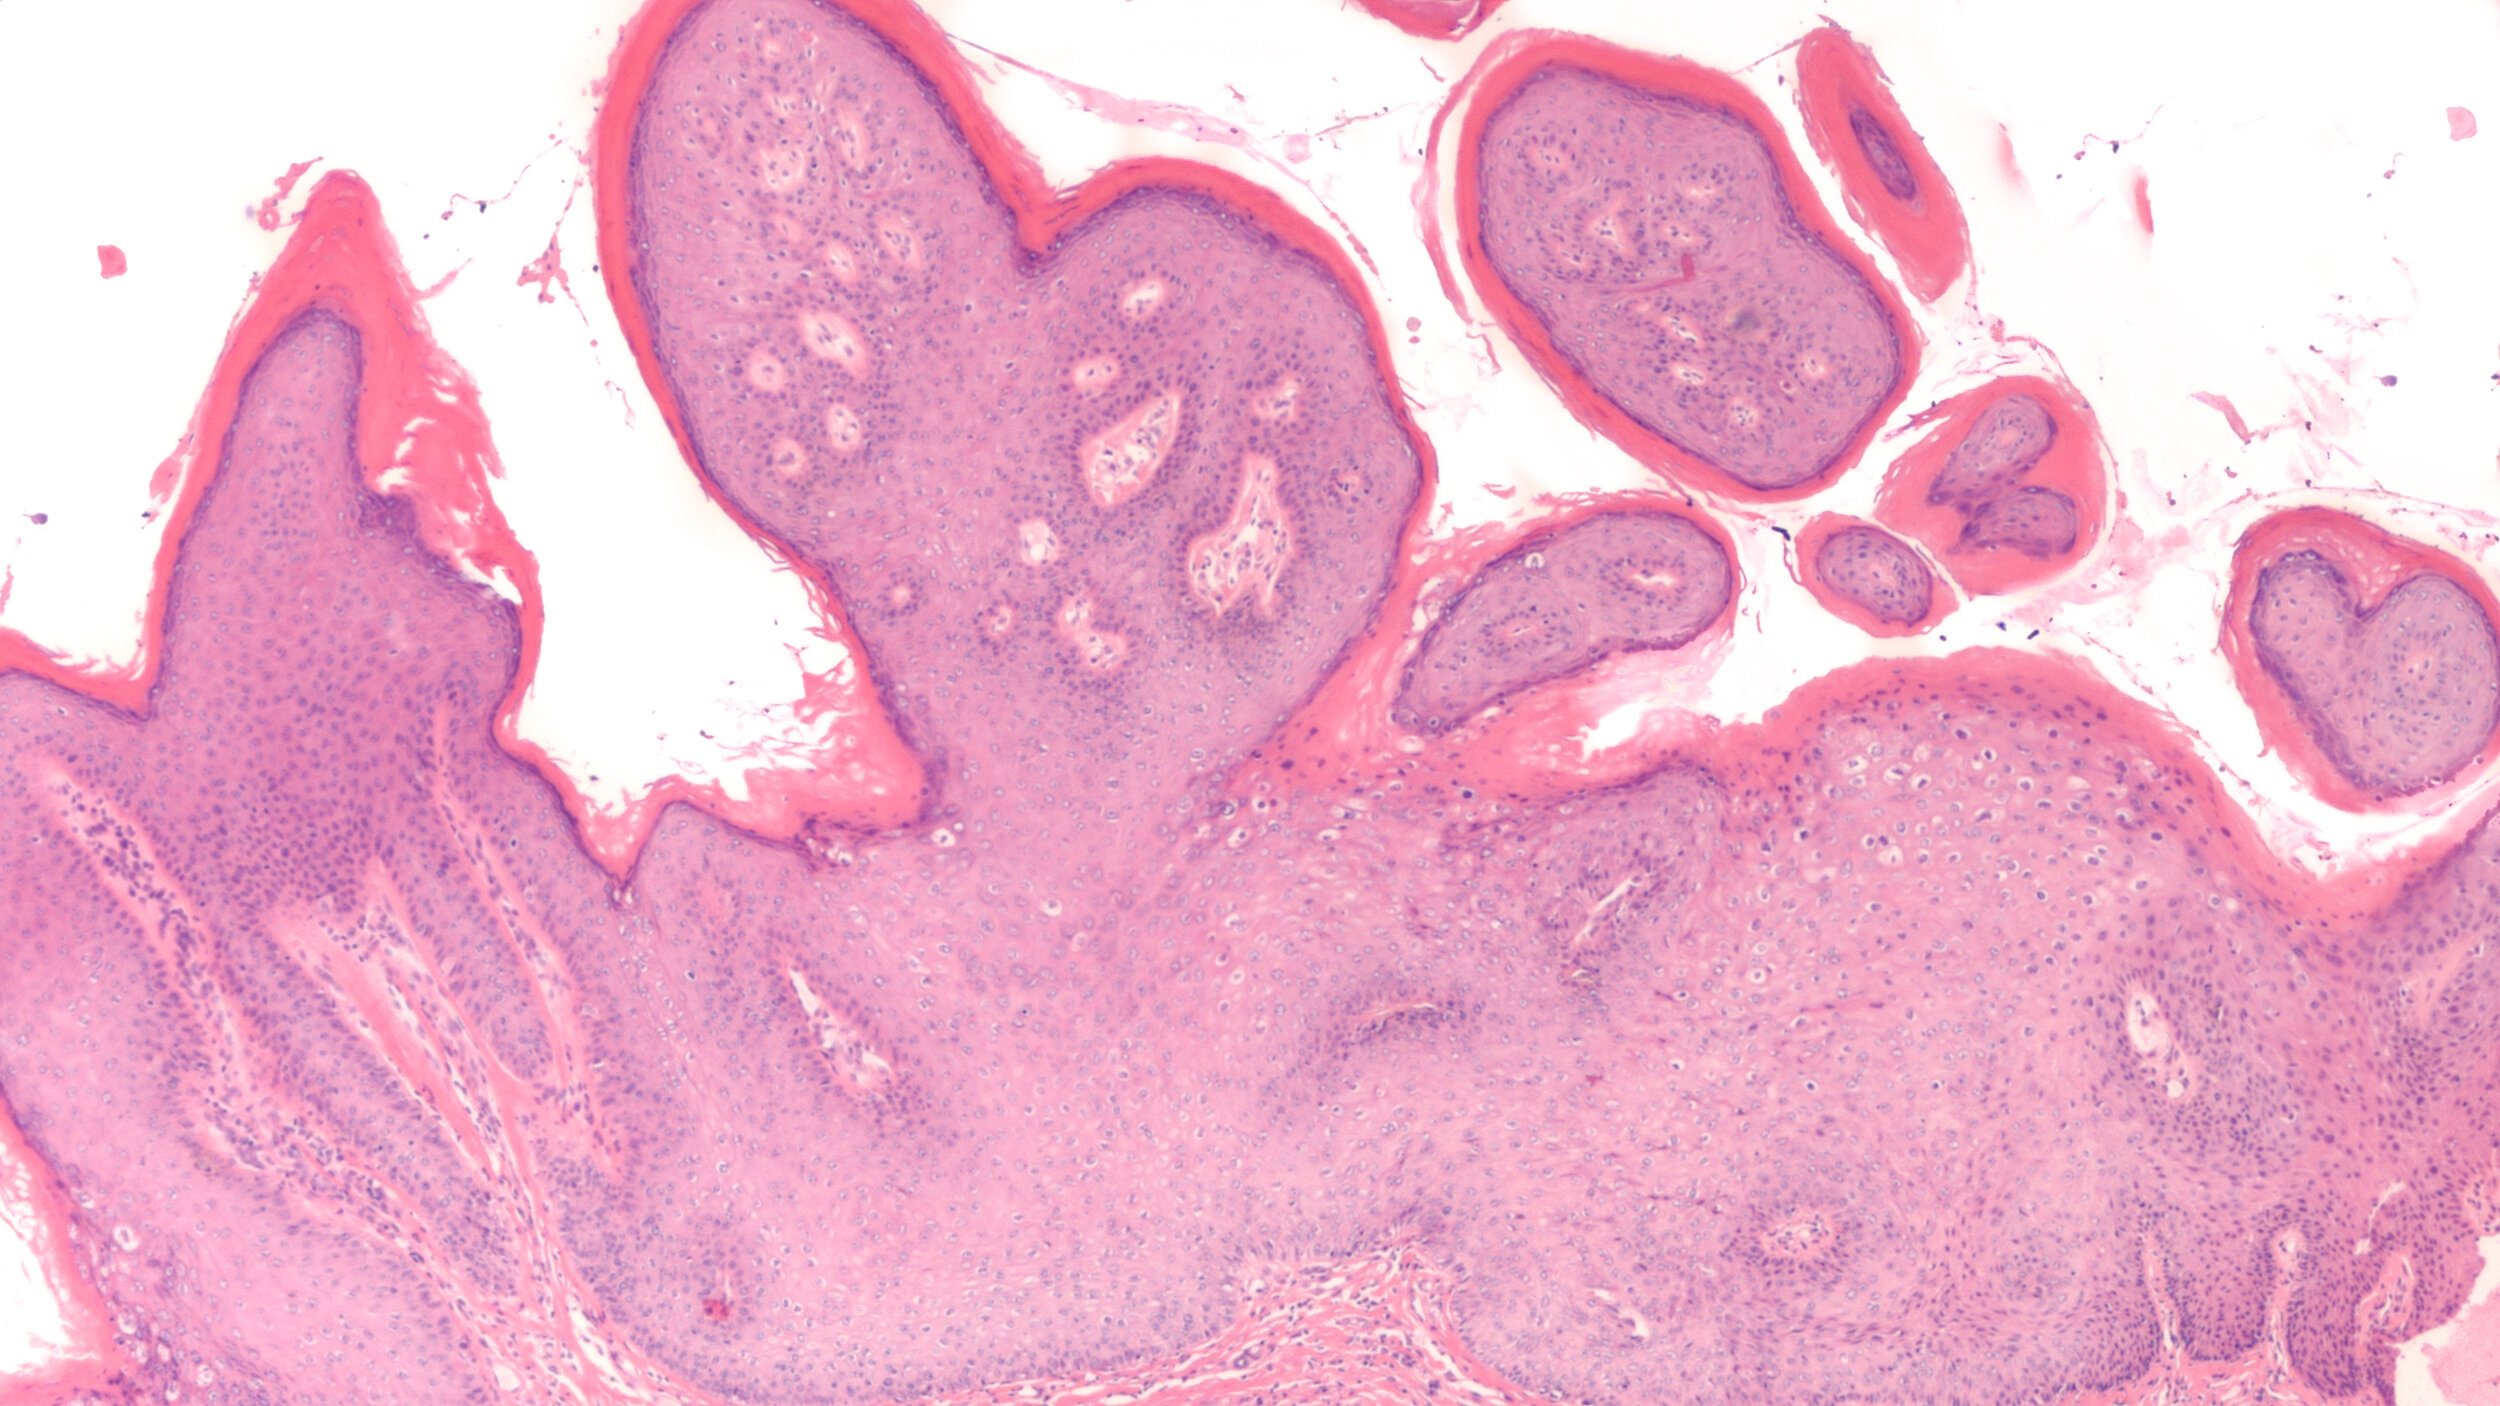

Microscopic image of condyloma accuminatum, also known as a genital wart, with low grade squamous intraepithelial lesion (LSIL, mild dysplasia, CIN 1) due to human papilloma virus (HPV)